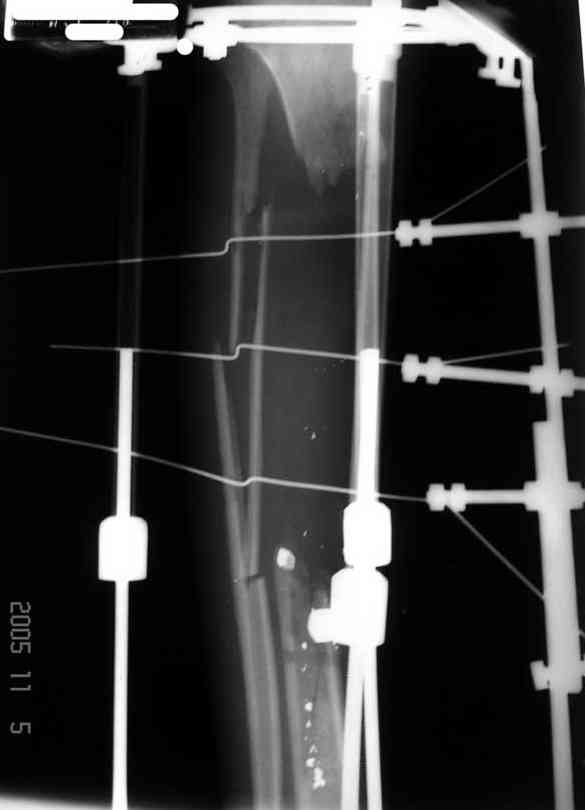

4. Никто не назвал методику, которая мне представляется наиболее удачной - тибиализация малоберцовой кости. Пластинку, конечно, придется убрать. Нужно наложить кольцевой Илизаров,

томировать малоберцовку на уровне дефекта, закрыто пересечь большеберцовую кость у основания острого края проксимального отломка - и подтянуть фрагмент малоберцовой кости в зону дефекта большеберцовой спицами с упорными площадками. Не обязательно при этом выводить строго в центр, достаточно сращения при боковом касании отломков - малоберцовая кость оттеснит как раз "сосульку" в сторону, и томированные края берцовых костей срастутся между собой. Есть еще ряд нюансов - готов расписать со схемами в случае, если будет принято решение в пользу этой методики.

Реализовал описанную выше методику, и в итоге вот что получилось. Высылаю лишь прямые проекции,

в боковых тоже всё в тему.

Очень пригодились карбоновые кольца (Джолдас -огромное спасибо, я твой должник!!!), поскольку остеопороз дистального отломка был просто невероятный. На цифровом рентгене с трудом угадывались контуры.

Рентген в процессе перемещения - внизу карбоновые кольца, тракция фрагмента спицами с упором.

внешний вид в аппарате - не завершающем этапе, сначала стопа тоже была фиксирована в аппарате.

Сейчас аппарат сняли, но случай ещё не завершенный.

Признаюсь честно, не совсем уверен в прочности консолидации на стыке косточек. Кроме того, укорочение в районе 6 см. Сейчас реабилитация - ходит опираясь на ногу с одним костылем.